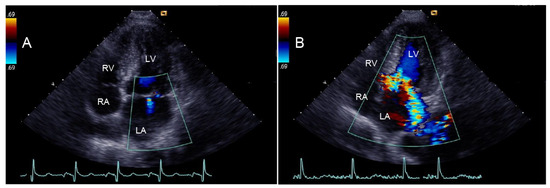

| Eccentric jet of MR—no. (%) | 52 (30) | 12 (10) | 40 (67) | <0.001 |